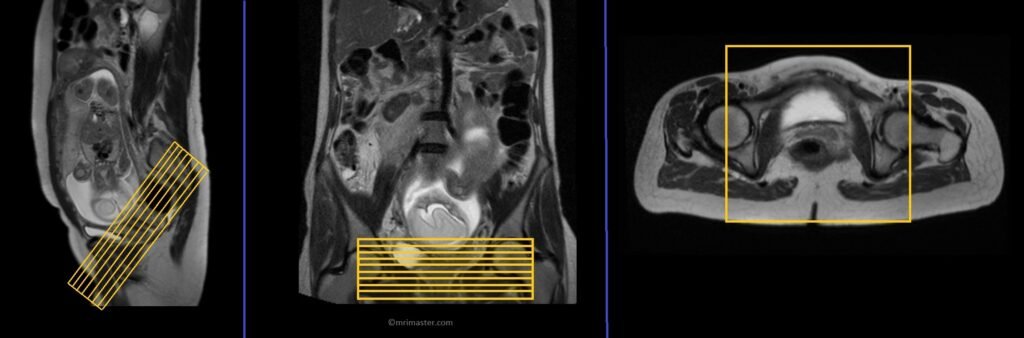

T2 HASTE axial oblique 4mm Respiratory gated

Plan the axial slices on the sagittal scans; angle the position block perpendicular to the birth canal. Verify the positioning block in the other two planes. Maintain an appropriate angle in the coronal plane, aligning it parallel to the right and left humeral head. Include enough slices to cover the entire birth canal.